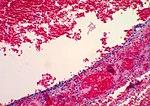

In case an ovarian cyst is surgically removed, a more definite diagnosis can be made by histopathology:

| Type | Subtype | Typical microscopy findings | Image |

|---|---|---|---|

| Functional cyst | Follicular cyst | .jpg)  | |

| Corpus luteum cyst |   | ||